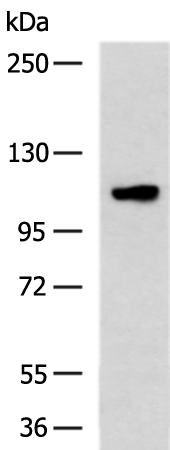

分类: 科研抗体货号: P10636别名: PI, A1A, AAT, PI1, A1AT, PRO2275, alpha1AT应用: WB,IHC反应种属: Human